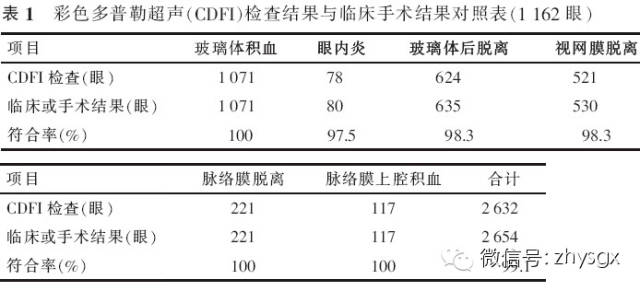

【摘要】 目的 探讨眼外伤所致眼内病理膜的彩色多普勒超声诊断特点。方法 回顾性病例研究。选择2013年1-12月因眼外伤行眼部彩色多普勒超声检查的患者1 156例(1 162眼),对其彩色多普勒超声诊断特点进行总结和分析,部分病例经手术确定诊断,判断彩色多普勒超声诊断的准确性。结果 1 156例(1 162眼)的超声诊断包括玻璃体积血(1 071 眼)、眼内炎(78眼)、玻璃体后脱离(624眼)、视网膜脱离(521眼)、脉络膜脱离(221眼)、脉络膜上腔积血(117眼)等。眼外伤所致的玻璃体内膜状病变的彩色多普勒超声诊断特点为单一疾病表现典型,但多数患者存在2种或2种以上病变。应用彩色多普勒超声检查,在参考二维超声检查结果的同时,根据视网膜、脉络膜的血供特点,可以在错综复杂的眼内条带状回声中分辨出脱离的视网膜和脉络膜,为手术和治疗提供可靠的依据。本组部分病例经手术治疗。总体超声诊断与临床和手术诊断的符合率为99.1%。结论 应用彩色多普勒超声检查眼外伤所致玻璃体内膜状病变是一种经济、简便、无创、可重复性好的诊断方法,根据视网膜和脉络膜的血流特征分析方法,可以提高超声诊断的准确性。

【Abstract】 Objective To investigate thecharacteristics of damage to intraocular membranes from ocular trauma usingcolor Doppler flow imaging (CDFI) for diagnosis. Methods Weretrospectively studied 1 162 eyes of 1 156 patients who sustained ocularinjuries from January 2013 to December 2013. CDFI was used to detect damage toocular membranes. The surgical diagnosis was also reviewed. Results Among 1 162 eyes of 1 156 patients, vitreous hemorrhage presented in 1 071 eyes, endophthalmitis presented in 78 eyes, andposterior vitreous detachment presented in 624 eyes. There were 521, 221 and 117 eyes with retinal detachment,choroidal detachment and choroidal hemorrhage,respectively. While trauma to intraocular membranes is typically associatedwith a single injury identified with CDFI, most of thepatients suffered from various injuries. Color Doppler flow imaging detectedthe damaged tissues with 2D images. Moreover, theimaging can analyze the retina and choroid blood flow to help distinguishretinal or choroidal detachment. In this study, 99.1%of the ultrasound diagnoses matched the clinical and surgical diagnoses.Conclusion Color Doppler flow imaging isan economical and simple way to detect intraocular membrane injury from oculartrauma. It is also noninvasive and repeatable. The use of retinal and choroidalblood flow analysis can increase the detection rate of intraocular membraneinjury from ocular trauma.